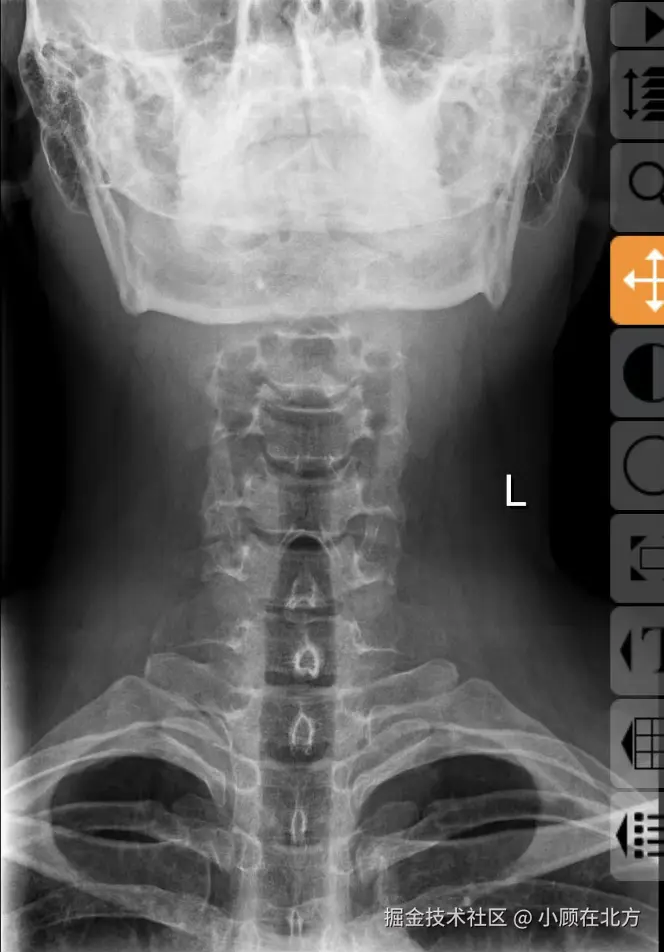

当时有点害怕,赶紧去了医院。先做了脑部CT,没查出问题。医生建议我去看看颈椎。拍了片子,结果出来了:颈椎有问题,我印象中是二三节那里。

原因很简单,就是长期坐着,姿势不对。

看着片子,我才真正意识到那句话:身体是革命的本钱。  对于我们这些天天和电脑打交道的人,颈椎和腰,就是最脆弱的环节。以前总觉得自己年轻,扛得住,现在才发现,有些损耗是不可逆的。